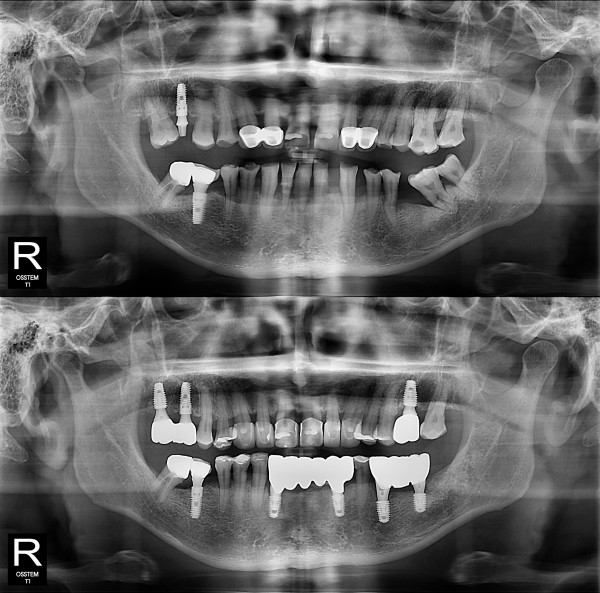

种植牙

局部种植牙